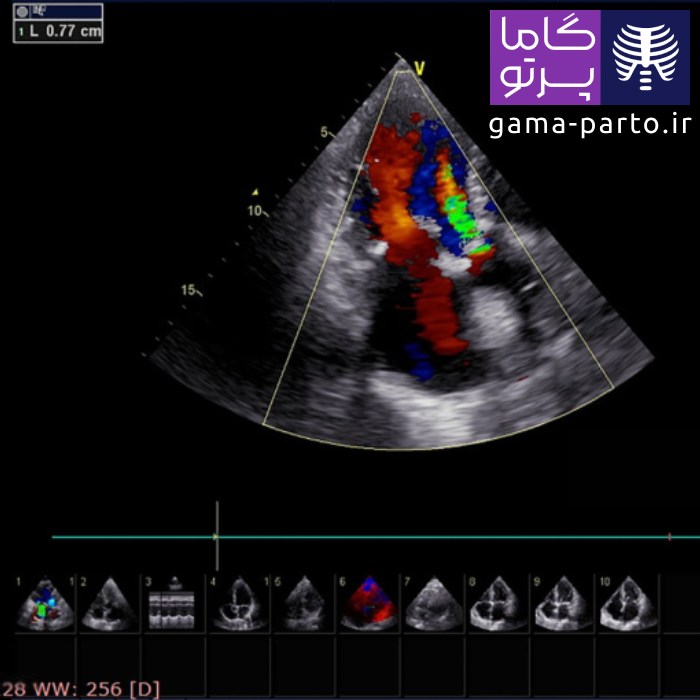

اکو قلب داپلر رنگی - Color Doppler Echocardiography

در تکنیک داپلر رنگی، دادههای مربوط به اندازه و شکل قلب (بهصورت دوبعدی) با اطلاعات داپلر طیفی ترکیب میشوند تا سرعت و جهت جریان خون با رنگهای مختلف نمایش داده شود. بهطور نمونه، رنگ قرمز نشاندهنده حرکت خون به سمت پروب است. این کدگذاری رنگی باعث میشود متخصص قلب بتواند بهسرعت اختلالات احتمالی را شناسایی کند. شایان ذکر است کیفیت تصاویر این روش در دستگاههای قابل حمل گاما پرتو بسیار بالا بوده و برای تشخیص دقیق مورد استفاده قرار میگیرد.